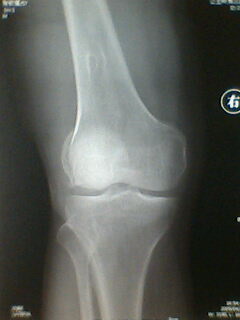

标题: X5658:膝关节改变?!

中年男性,外伤,疼痛!

股骨下段骨软骨瘤。撕脱性骨折

支持考虑骨软骨瘤,髁上突在肱骨内髁上方.本例股骨外髁关节面似有异常,但是可以是与髌骨重叠构成,必要时加照正位(稍内斜一点把髌骨让开)

宽基底与股骨干相连,背离关节面,支持考虑股骨下段外生骨疣

第二楼的回答是全面和正确的!

髌骨向外下移位,股骨下段骨软骨瘤。